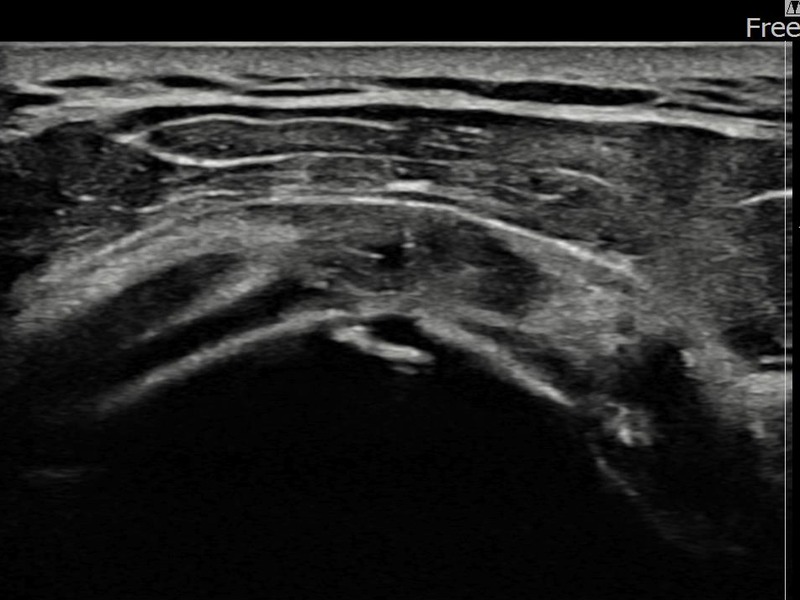

김ㅇㅇ님 · 좌측 극상근건 광범위 부분파열

좌측 어깨 광범위 파열로 수술을 권유받았으나 비수술 치료를 원해 내원하셨습니다. 초음파 검사에서 극상근건 전층에 걸친 광범위 부분파열이 확인되었으며, 어깨인대 축소봉합술 후 구조적 안정화와 기능 회복이 이루어졌습니다.